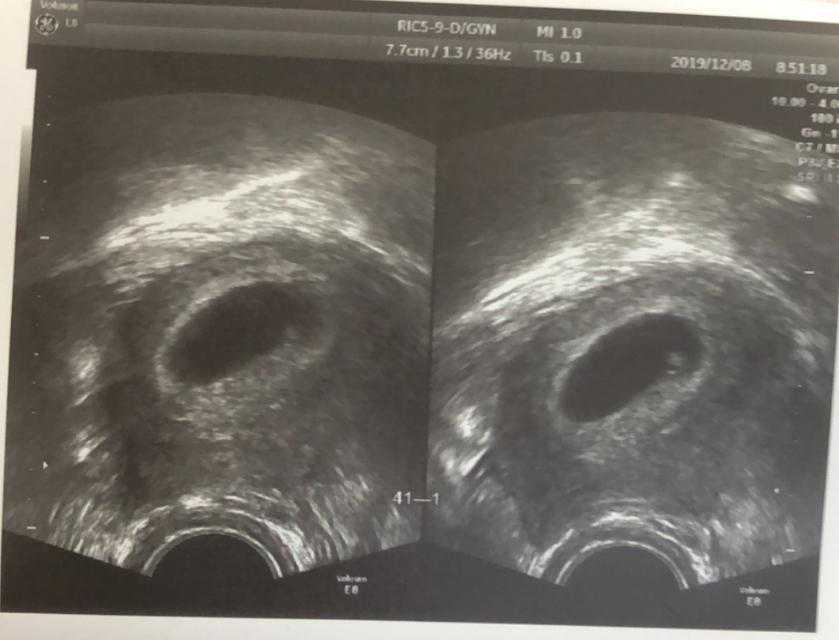

一些患者多年不孕,想要通过试管技术助孕,但接受检查后发现自己基础卵泡少,就很担心这种情况会影响自己做...

最近,有很多患者在线咨询试管婴儿取卵后卵巢多久能恢复正常?及试管婴儿取卵后注意什么?试管婴儿取卵后如...